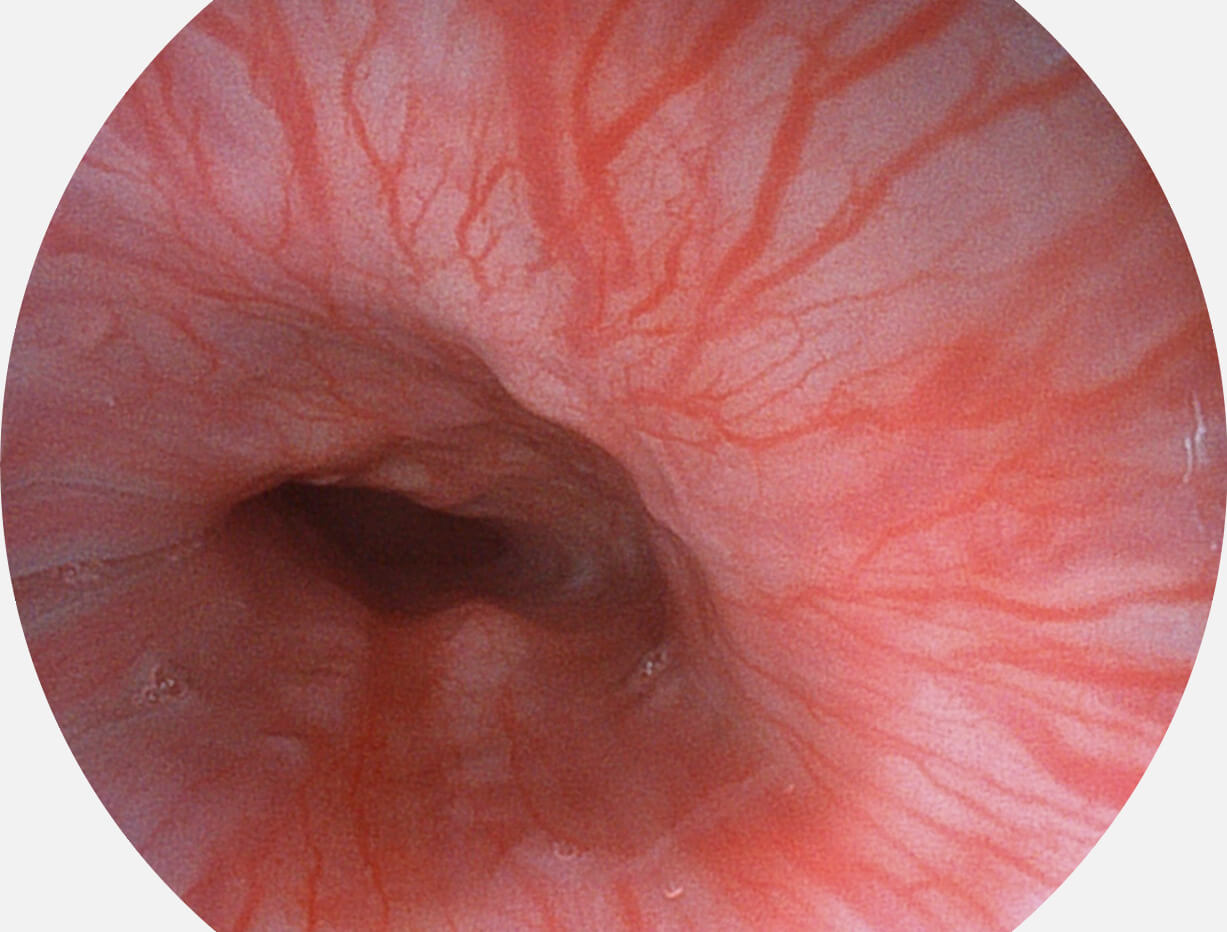

强调浅层黏膜结构的同时,保证照明亮度和提升浅层微血管与中层血管颜色对比度,病变边界更清晰。

• 白光图像 VIST图像